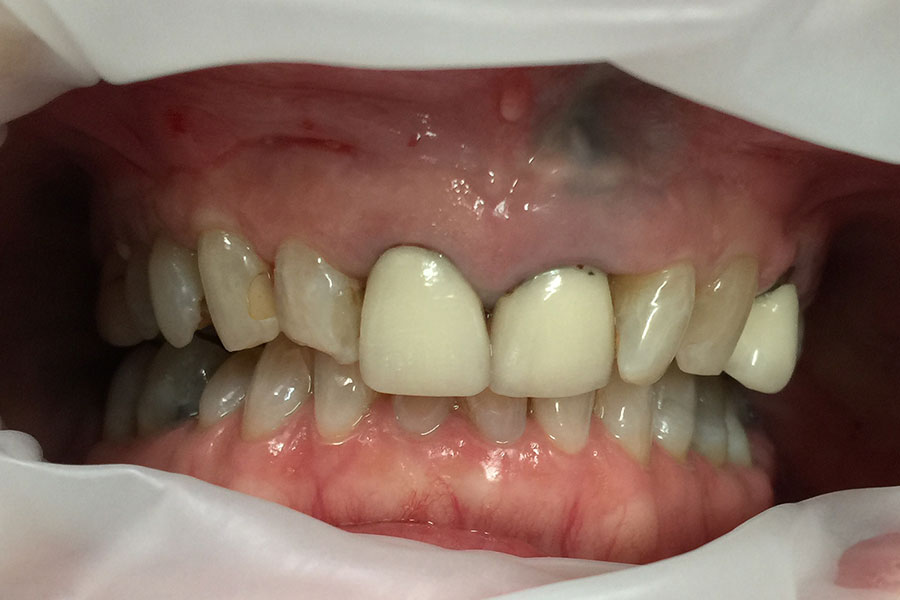

Brooke had a single crown on the upper left central incisor that had a receding gum line.

Some of the white fillings on other front teeth were also stained. Deb decided to have the crown replaced and ceramic veneers placed on other teeth. The new crown on the upper left central incisor is all ceramic (without any metal on the inside) and blends in more naturally with the veneers.